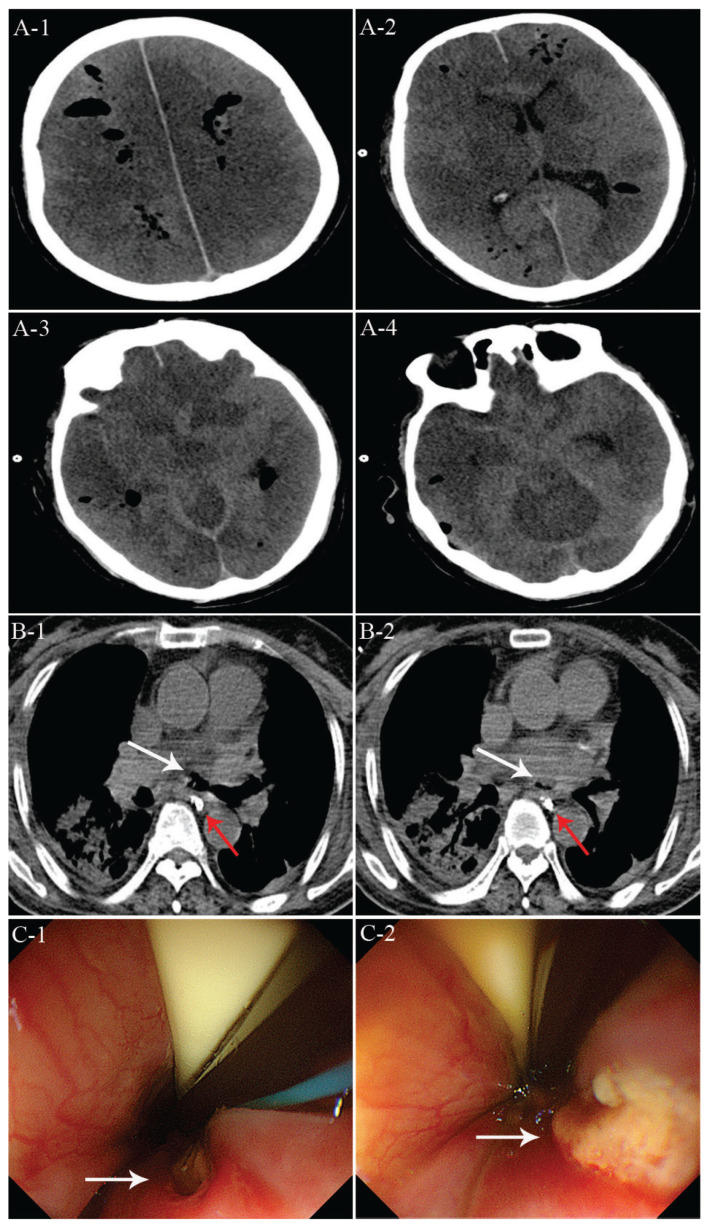

Air embolism resulting from atrioesophageal fistula following thoracoscopic atrial fibrillation ablation.

胸腔镜房颤消融后心房食管瘘所致空气栓塞。